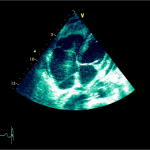

Ecocardiografia transtoracică

- Formaţiune hiperecogenă cu suprafaţa neregulată, care tapetează peretele liber al VD, grosime de 12 mm

- Dispusă de sub planul valvei tricuspide până in apropierea conului de ejecţie al valvei pulmonare

- SIV aplatizat

Ecografia transesofagiană:

Confirmă datele de la ecografia transtoracică